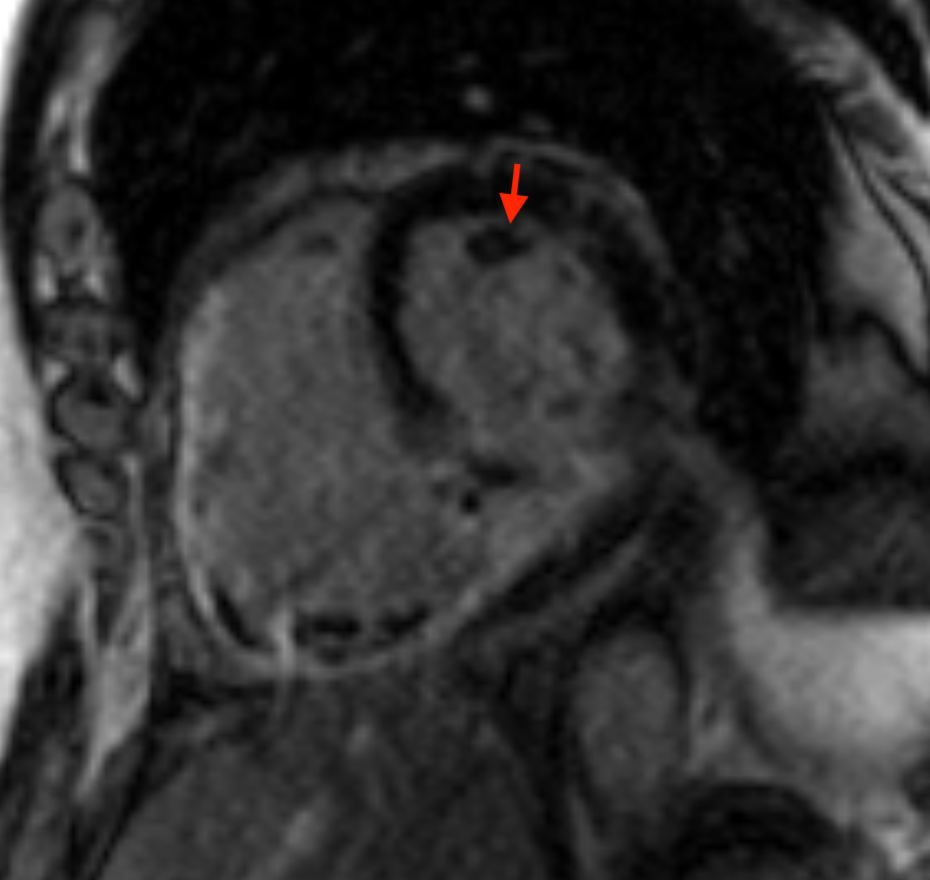

Ισχαιμική μυοκαρδιοπάθεια.

Εικόνα απο μαγνητική τομογραφία καρδίας μετα από έμφραγμα του οπίσθιου καρδιακού τοιχώματος με δημιουργία θρόμβου